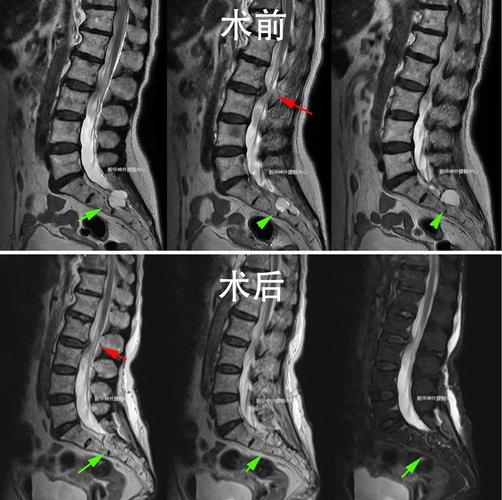

骶管囊肿手术过程图片